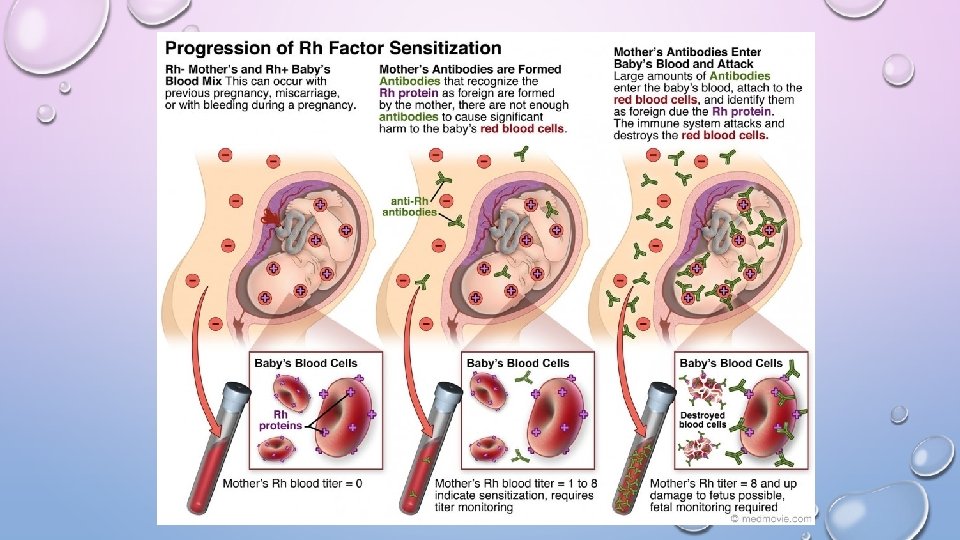

RH FACTOR • RHESUS MONKEY EITHER YOU HAVE THE PROTEIN (+) OR NOT (-)